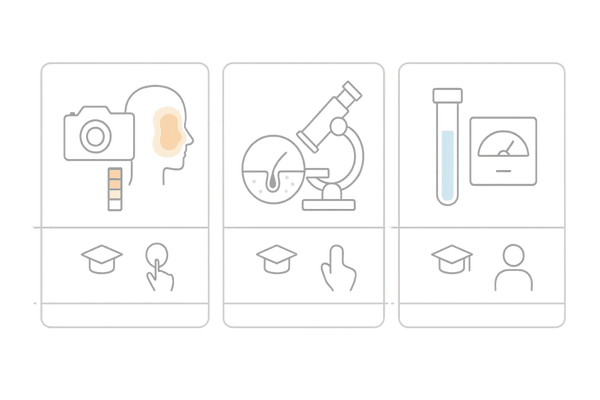

他の薄毛検査とサーモグラフィーの違い

薄毛の原因を調べるためには、さまざまな検査方法が存在します。マイクロスコープによる頭皮の拡大観察や、血液検査、遺伝子検査など、それぞれに目的と特徴があります。

サーモグラフィー検査は、これらの検査と組み合わせることで、より多角的に原因を究明するのに役立ちます。

ここでは、他の主要な検査とサーモグラフィーの違いを比較し、その独自の利点を解説します。

マイクロスコープ検査との比較

マイクロスコープ検査は、頭皮や毛穴の状態を200倍以上に拡大して観察する方法です。毛穴の詰まり具合、皮脂の分泌量、頭皮の色、炎症の有無、髪の毛の太さなどをミクロな視点で詳細に確認できます。

一方、サーモグラフィーは頭皮全体の血行状態というマクロな視点での評価を得意とします。

マイクロスコープが「頭皮の表面」の状態を見るのに対し、サーモグラフィーは「頭皮の内部」の血流を見る検査、と考えると分かりやすいでしょう。

血液検査との比較

血液検査では、髪の成長に影響を与える可能性のある体内の状態を調べます。例えば、貧血の有無(鉄分不足)、甲状腺機能、栄養状態(タンパク質や亜鉛など)、ホルモンバランスなどを数値で評価します。

これは全身的な健康状態が髪にどう影響しているかを知るための重要な検査です。

サーモグラフィーは、こうした全身の状態が結果的に「頭皮の血流」にどのような影響を及ぼしているかを視覚的に捉えることができます。

血液検査が「原因」を探るのに対し、サーモグラフィーは「結果」として現れる頭皮の状態を確認する役割を担います。

遺伝子検査との比較

遺伝子検査は、主に男性型脱毛症(AGA)の発症リスクを評価するために行います。特定の遺伝子を調べることで、将来的にAGAを発症しやすい体質かどうかを予測します。

これはあくまで「リスクの高さ」を知るためのものであり、現在薄毛が進行している直接的な原因を特定するものではありません。

サーモグラフィーは、遺伝的リスクの有無にかかわらず、「現在」の頭皮の血行状態を評価し、薄毛が進行している現場で何が起きているのかを明らかにします。

各検査方法の比較

| 検査方法 | 主な目的 | わかること |

|---|---|---|

| サーモグラフィー | 頭皮全体の血行評価 | 血流の分布、温度異常、血行不良部位 |

| マイクロスコープ | 頭皮・毛穴の拡大観察 | 毛穴の詰まり、皮脂量、炎症、髪の太さ |

| 血液検査 | 全身の栄養・ホルモン状態の評価 | 貧血、栄養不足、甲状腺機能、ホルモン値 |

サーモグラフィー検査の独自の利点

サーモグラフィー検査には、他の検査にはない独自の利点があります。それは「非侵襲的」かつ「広範囲」を「リアルタイム」で評価できる点です。

採血のような痛みも、マイクロスコープで頭皮を押さえるような物理的接触もありません。そして、頭皮全体の状態を一度に画像として捉えられるため、問題のある箇所を直感的に把握できます。

また、施術前後の血行の変化を比較することで、育毛剤やマッサージなどのケアが実際に効果を上げているかを客観的に評価するツールとしても活用できます。